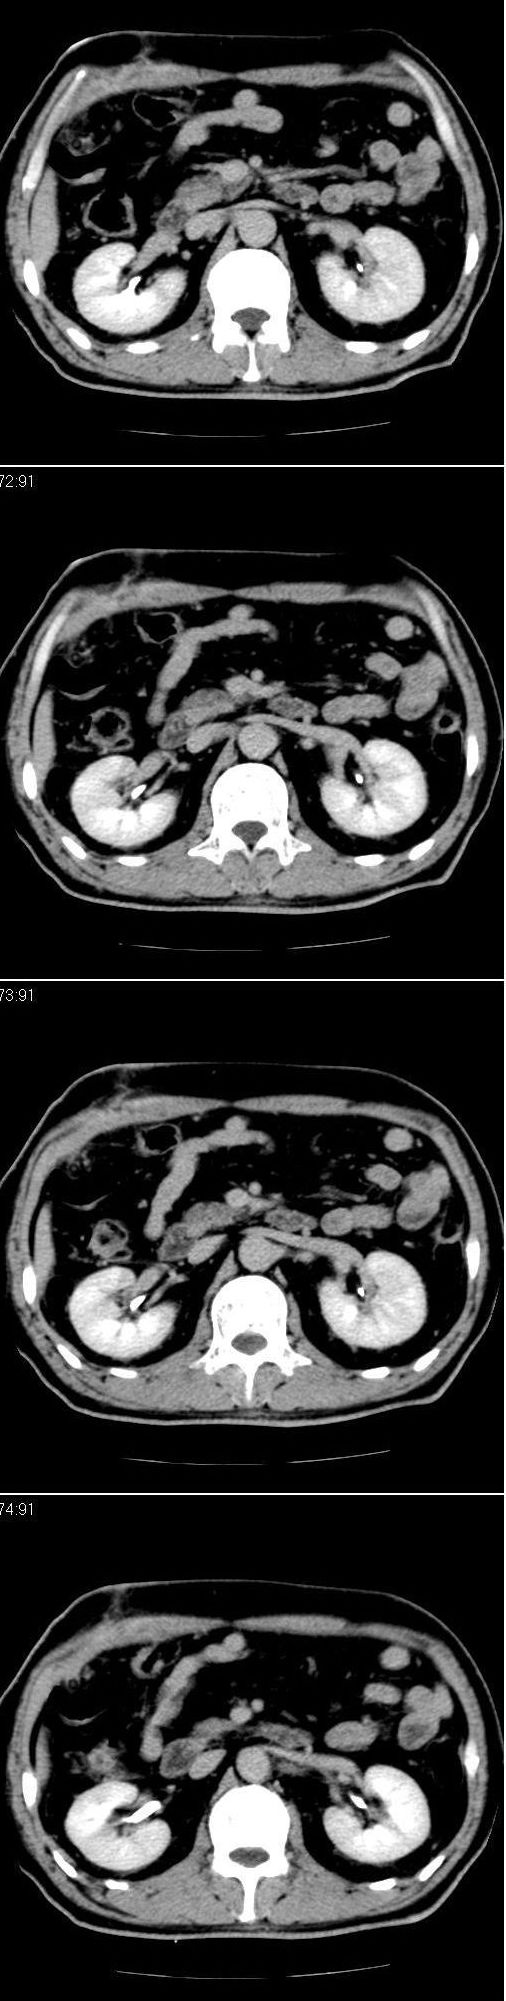

男,57岁。因胆结石阻塞性黄疸入院。这是胆囊切除术后的照片,看看此片到底有什么问题。

胆总管有没有问题,尤其是肝门附近的胆总管?

肝门附近的胆总管轻度扩张 请楼主复习术前片

肝内外胆管轻度扩张,胆囊窝内见引流管考虑胆囊切除术后改变.胃窦部软组织似增厚,建议胃镜检查.

在手术切除胆囊的过程中,发现肝门部胆总管恶性占位,因为家属不同意手术,没有切除,能看出来么?

现有资料很难说,薄层可能清楚些,如临床不提供,易诊断为术后改变。

不是楼主提醒还真看不出来,肝内胆管扩张。略显僵硬。

肝内外胆管轻度扩张。楼主提示左右肝管合汇区域壁稍厚。胆总管末段壁似也稍厚有轻度强化。就现有资料诊断难。